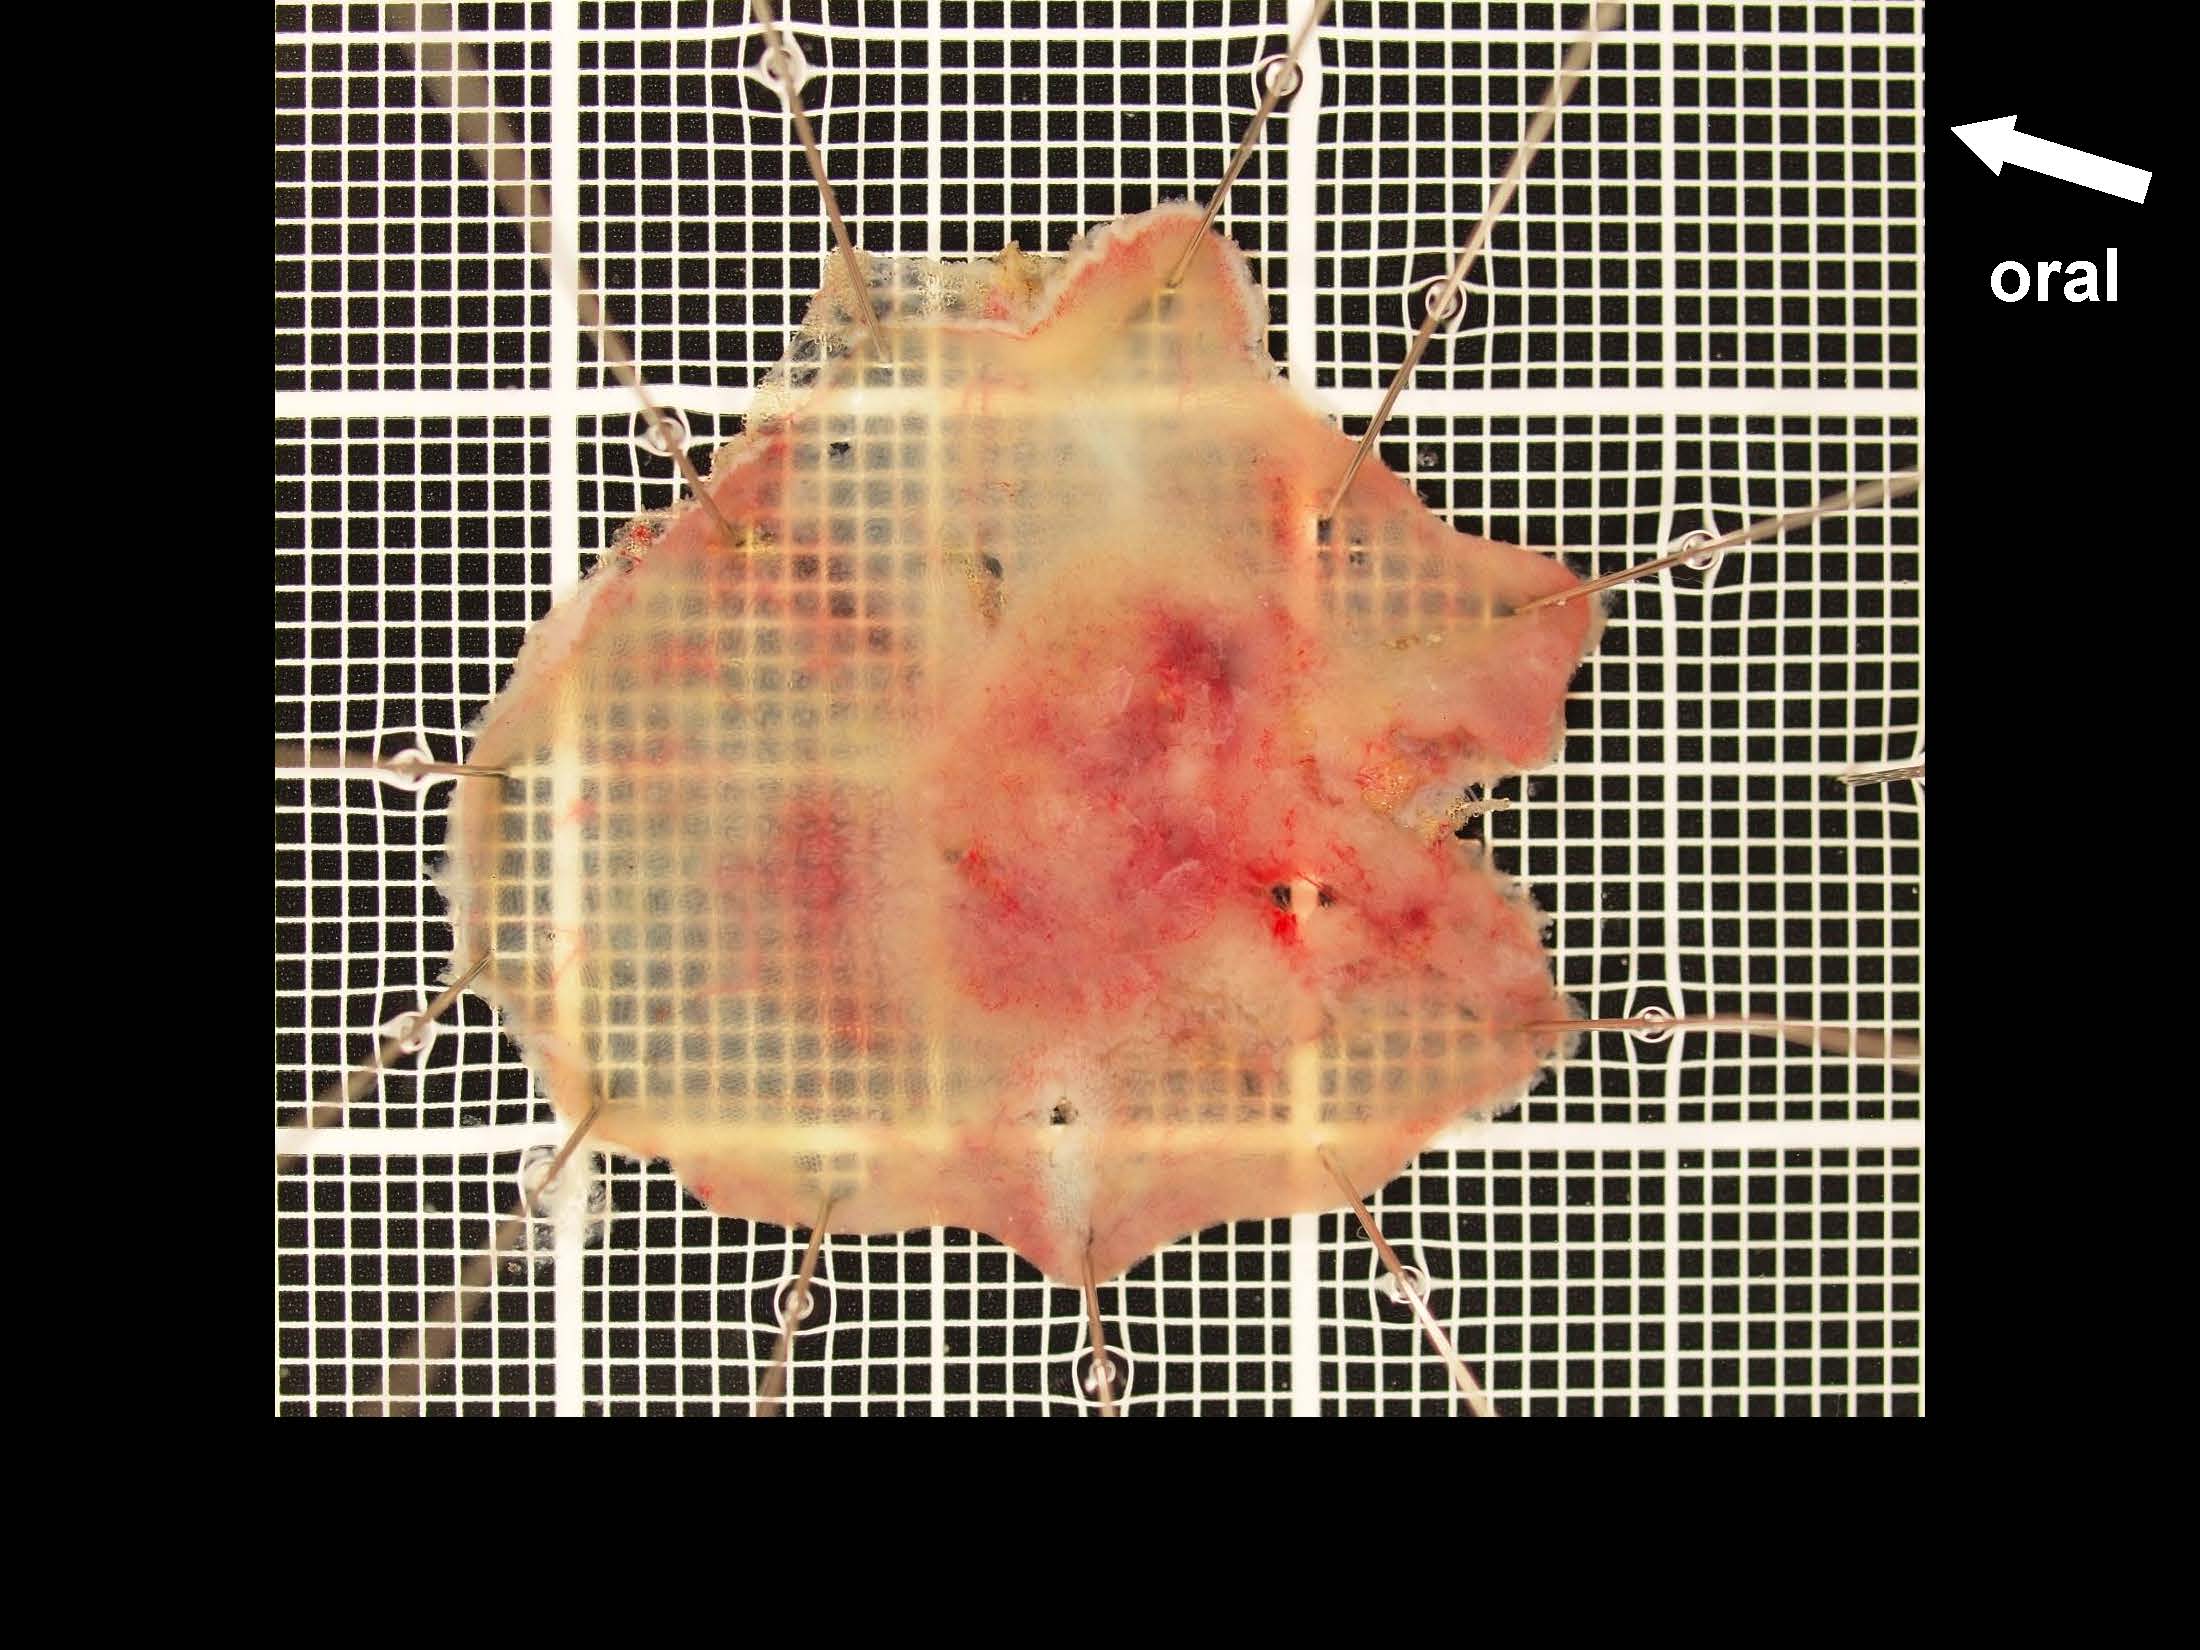

消化管Mapping~大腸~ 2021.10.27

消化管Mapping

消化管Mapping~大腸~

消化器内科

内視鏡検査・治療